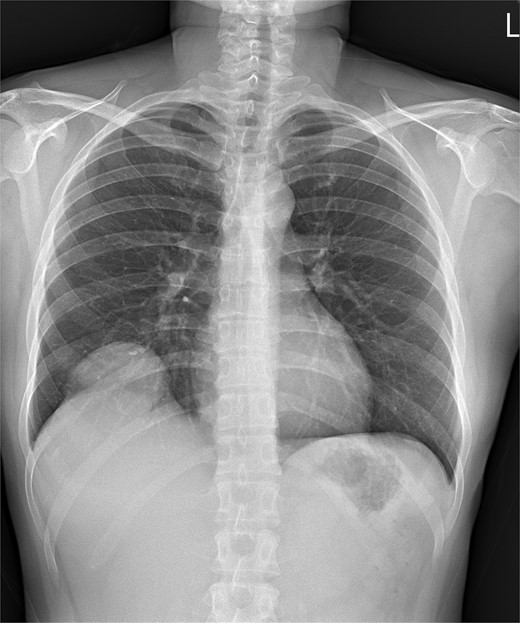

A 35-year-old woman with a history of prior alcohol use and tobacco smoking presented with a 2–3 month history of right shoulder pain, followed by generalized weakness, poor appetite, and abdominal discomfort. She also reported right rib pain, unintentional weight loss (3 kg within 3 months), and night sweats. She denied fever, upper respiratory infection symptoms, chest pain, shortness of breath, abdominal pain, dysuria, or diarrhea. Initial investigations at another hospital, including a chest X ray (Fig. 1), abdominal computed tomography (CT) scan, revealed a hepatic mass at segment 8 (S8). Tumor markers, hepatitis B virus, and hepatitis C virus serologies were negative.

Chest X ray image of sarcomatoid cholangiocarcinoma with direct invasion into the diaphragm and lung.